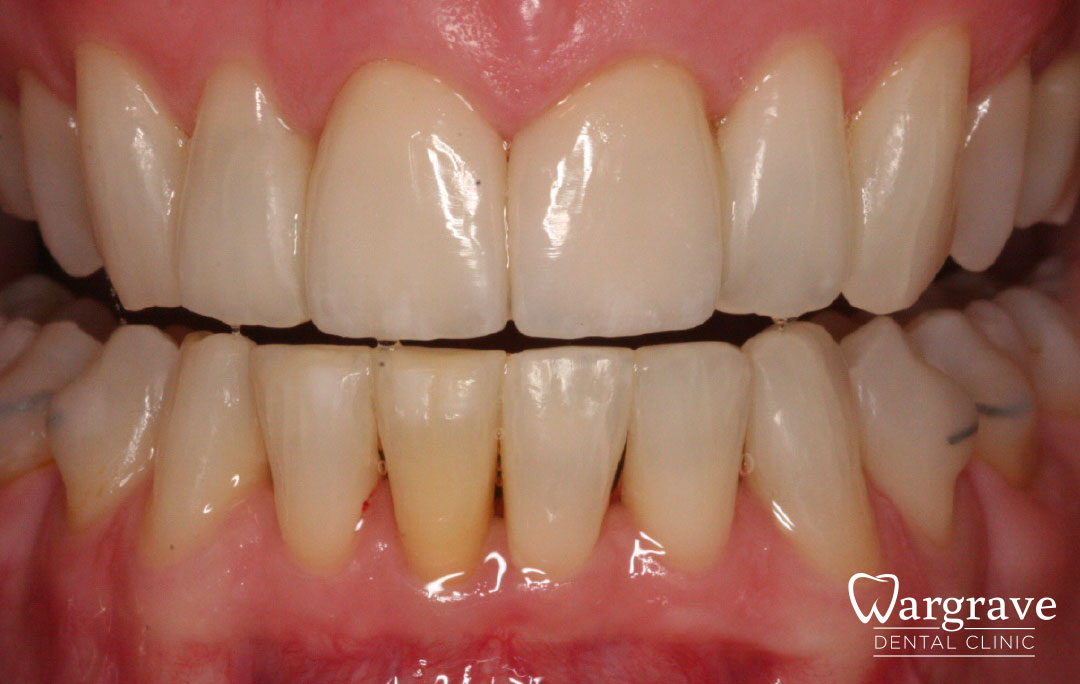

Healthy Smiles These are more advanced examples of different treatments available.All cases shown were carried out by Dr R Khurana unless otherwise stated. Immediate implants Anterior Mandible Bone Regeneration Anterior Mandibular Implant Bridge Maxillary Anterior Implant Bridge Implant stabilised ‘Life Like’ replacement dentures Implant Bridge after 10-years with zero bone loss Implant examples including ZBLC concepts Adhesive Bridge solution for a missing premolar Multidisciplinary care Orthodontics, Replacement veneers and composite bonding Adhesive Bridge solution for missing central incisors Replacement crown, Veneer and Composite Bonding Replacement Crowns and Veneer Injection Moulding using Composite Resin Equilibration Tooth Whitening to treat Developmental Discolouration